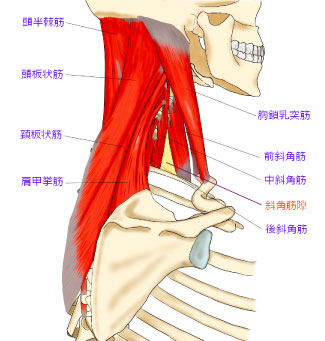

筋膜とは何か?

筋膜とは、筋肉を包む薄い膜のこと。

鶏肉をさばいたことがある方は、薄い透明の皮のようなものを見たことがあるかもしれません。

あれが「筋膜」です。

この膜は、筋肉の形を保ったり、他の組織と滑らかに動くようにサポートする役割を持っています。

よくあるのは、肩甲骨の内側や腱鞘炎を起こしやすい前腕の筋膜です。